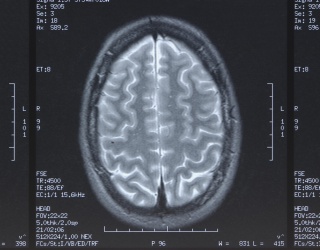

MRI Connectivity Patterns May Help Predict TBI Recovery

X-Rays Enable High-Resolution 3D Brain Mapping at PSI